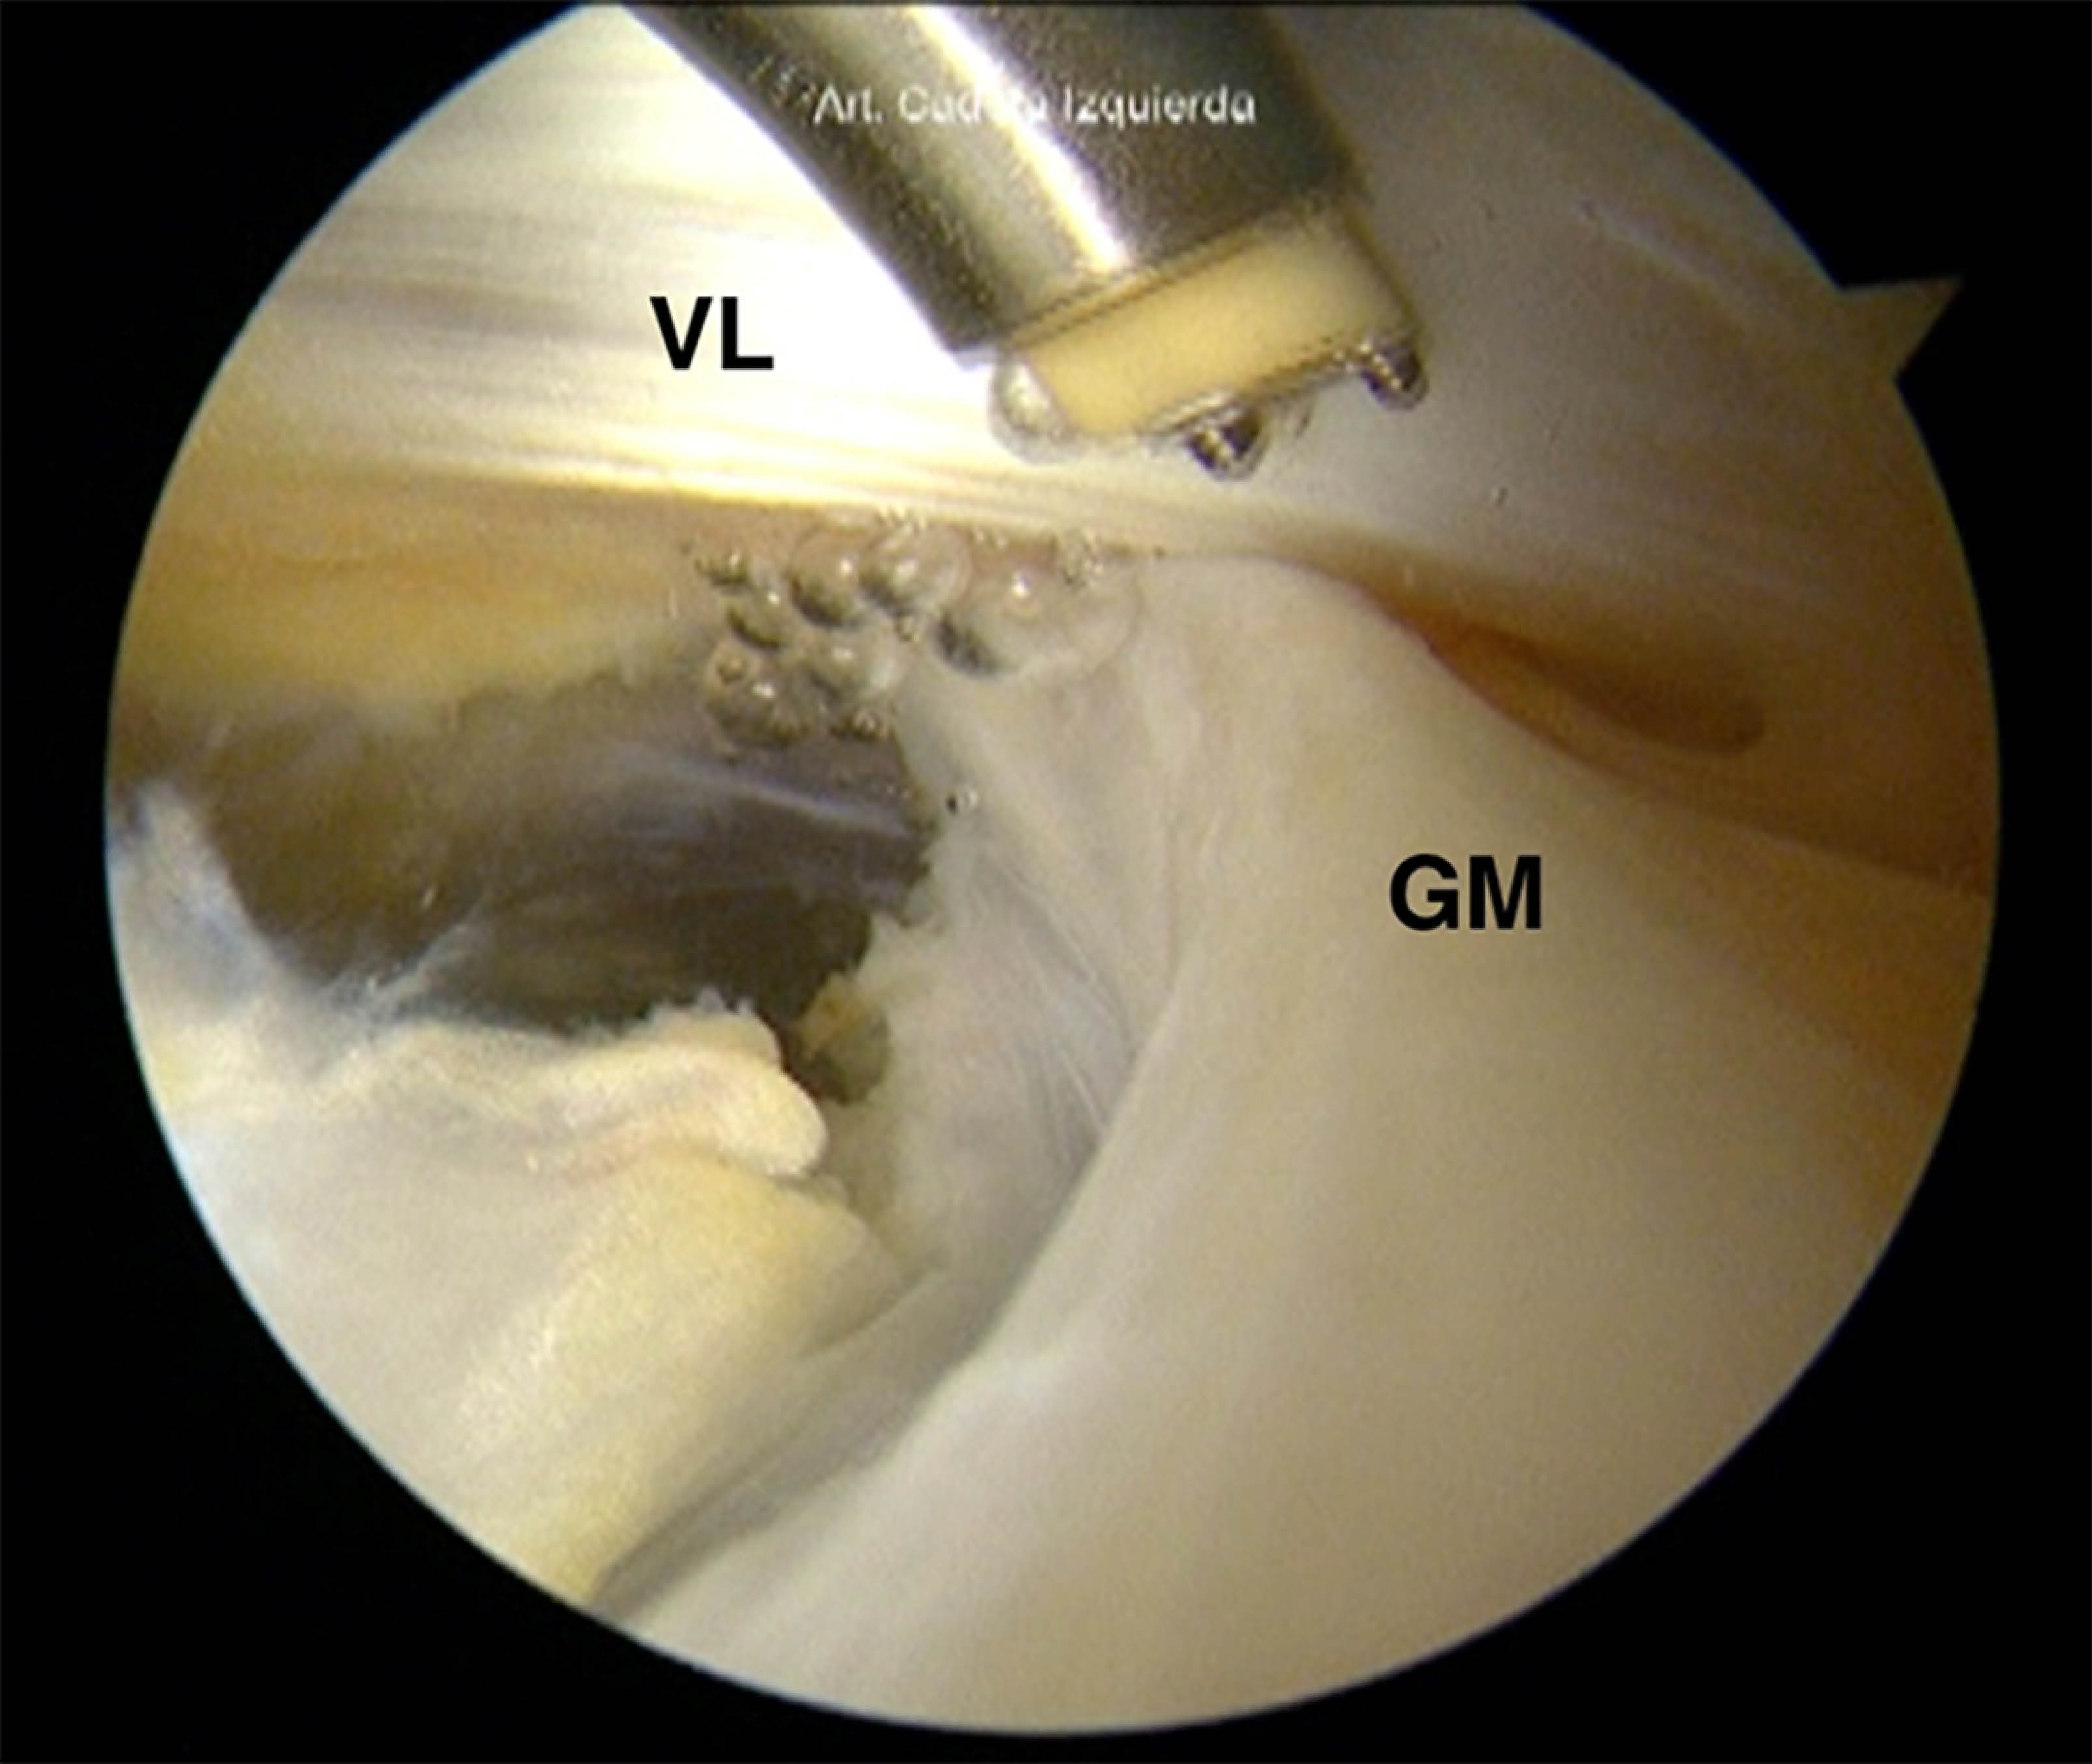

Liberación endoscópica del glúteo mayor para la descompresión peritrocantérica

Introducción: el síndrome peritrocantérico, también conocido como síndrome de dolor del trocánter mayor, afecta al 10-25% de la población y provoca dolor y deterioro funcional en la región lateral de la cadera. Esta afección suele estar asociada a discapacidades significativas a largo plazo. Objetivo: este estudio tiene como objetivo presentar un nuevo enfoque quirúrgico para el tratamiento del síndrome peritrocantérico que minimiza la invasividad y mejora los resultados para los pacientes. Material y métodos: describimos una técnica que utiliza portales personalizados a través de la banda iliotibial (BIT) junto con la liberación de la inserción proximal del glúteo mayor (GM). Los pacientes se colocan en posición supina, con acceso al espacio peritrocantérico mediante un artroscopio de 70°. Se realiza una liberación por radiofrecuencia de aproximadamente 3-4 cm de la inserción distal del GM para aliviar la presión y reducir la fricción en el espacio peritrocantérico. Conclusión: el método quirúrgico propuesto ofrece una alternativa prometedora a los enfoques tradicionales para el tratamiento del síndrome peritrocantérico, ya que minimiza el traumatismo tisular y mejora la recuperación. Es necesario realizar más investigaciones para evaluar la eficacia y la seguridad a largo plazo de esta innovadora intervención en una población de pacientes más amplia.

Figura 2